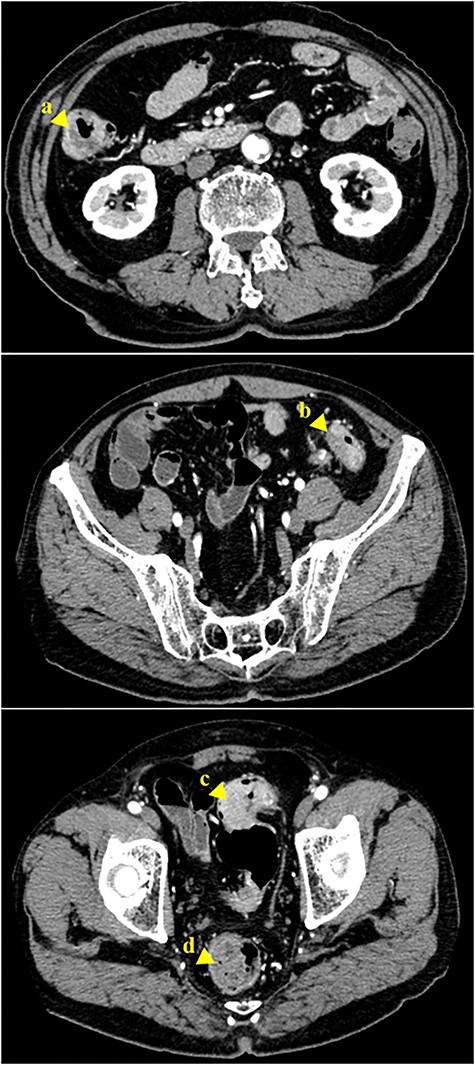

The surgical specimens of the ascending colon cancer (a), descending colon cancer (b) and the two sigmoid colon cancers (c and d).

During the operation, laparoscopic exploration confirmed the presence of known four tumors with no invasion of the serosa. Subsequently, a right hemicolectomy and sigmoid colectomy were performed laparoscopically. The right half of the colon was separated, and a side-to-side anastomosis between the jejunum and transverse colon was performed, followed by the sigmoid colon, and a colorectal anastomosis between the descending colon and rectum was performed. The resected tissue specimens revealed four tumors (Fig. 4). Histological examination showed that the first tumor in the ascending colon, the second tumor in the descending colon and the third tumor in the sigmoid colon had invaded up to the subserosa, whereas the fourth tumor in the sigmoid colon had invaded up to the muscularis propria (Fig. 5).